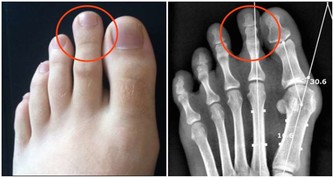

性功能障礙≠腎虛

很多人陷入了同一個誤區,認為男人性功能差就是腎虛,其實這是錯誤的。